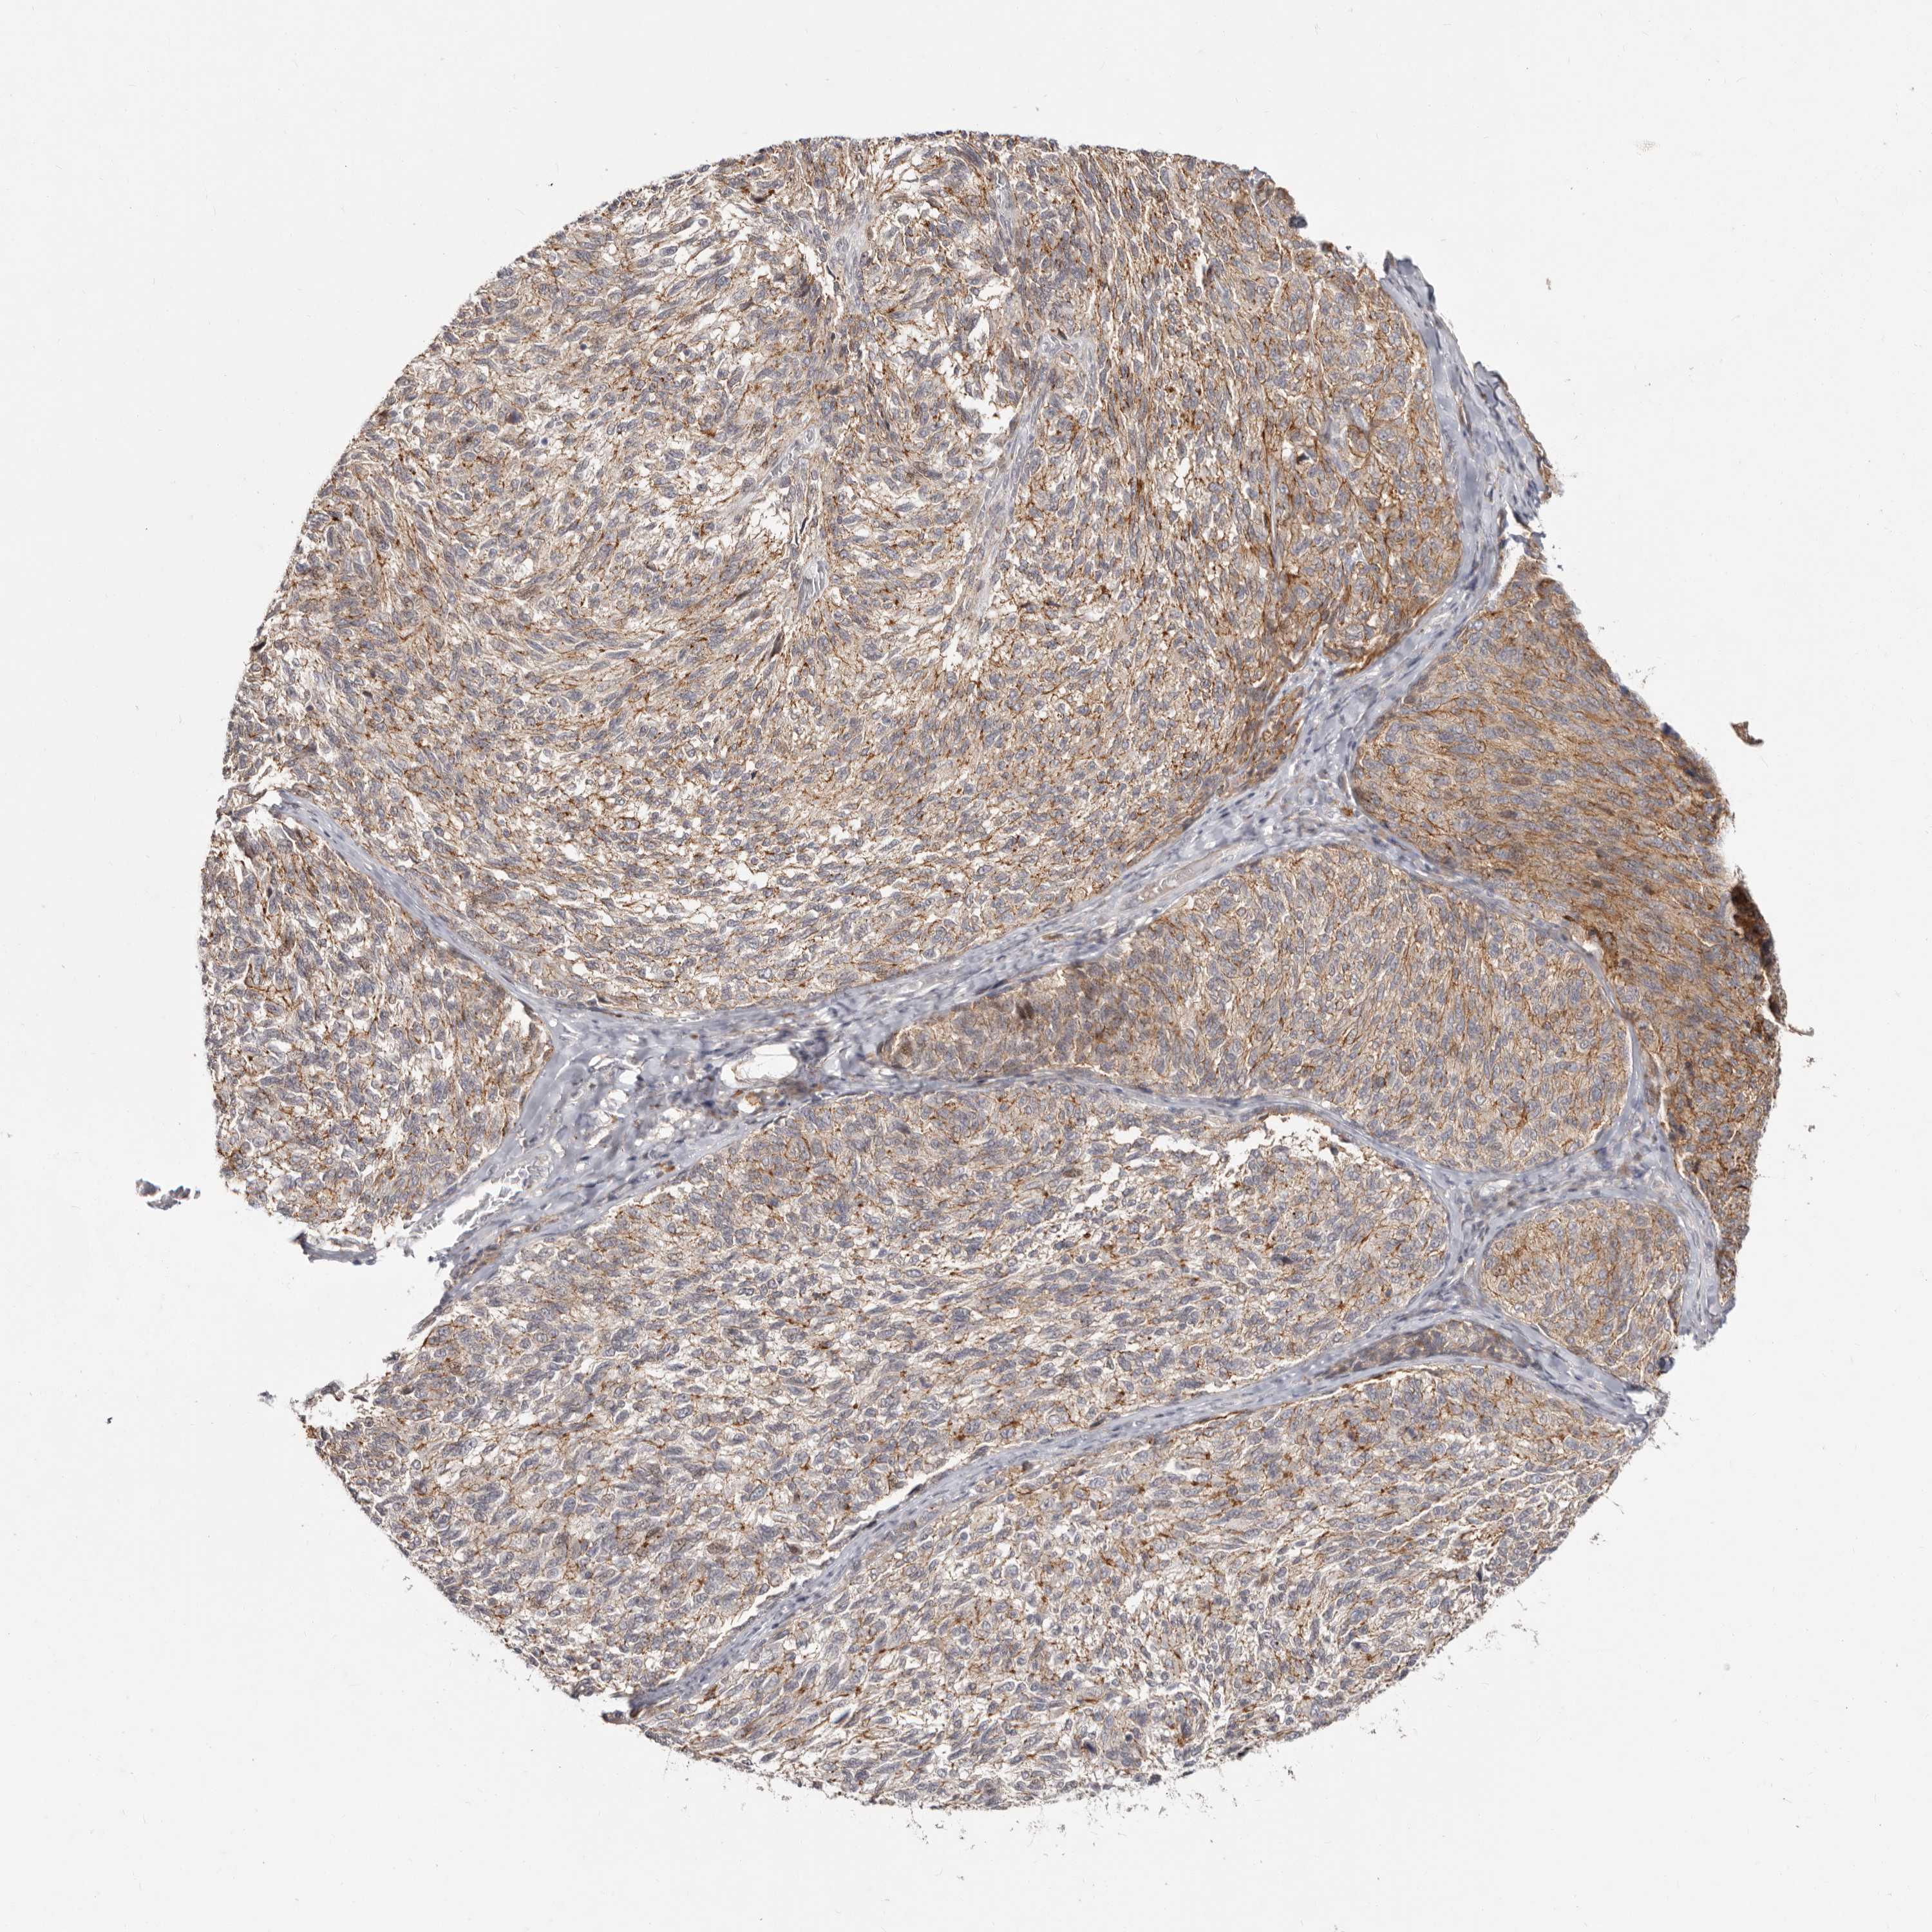

MELANOMA - Protein expressioni

A mouse-over function shows sample information and annotation data. Click on an image to view it in a full screen mode. Samples can be filtered based on level of antibody staining by selecting one or several of the following categories: high, medium, low and not detected. The assay and annotation is described here.

Note that samples used for immunohistochemistry by the Human Protein Atlas do not correspond to samples in the TCGA dataset.

Antibody stainingi

Antibody staining in the annotated cell types in the current human tissue is reported as not detected, low, medium, or high, based on conventional immunohistochemistry profiling in selected tissues. This score is based on the combination of the staining intensity and fraction of stained cells.

Each image is clickable and will lead to virtual microscopy that enables deeper exploration of all samples and also displays staining intensity scores, fraction scores and subcellular localization as well as patient and tissue information for each sample.

Antibody HPA029012

Staining

High

Medium

Low

Not detected

Intensity

Strong

Moderate

Weak

Negative

Quantity

>75%

75%-25%

<25%

None

Location

Nuclear

Cytoplasmic/membranous

Cytoplasmic/membranous,nuclear

Malignant melanoma, NOS

Malignant melanoma, Metastatic site